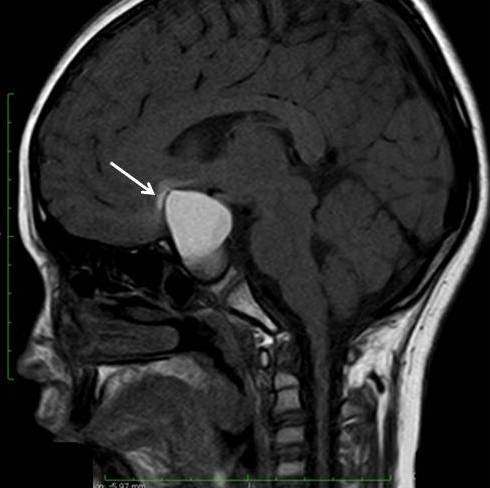

A 12-year-old girl presented with complaints of severe headache associated with vomiting for four days. She also gave a history of reduction in vision (Left>Right) and occasional mild headache of six months’ duration. She had no meningeal signs, fever nor neurological deficit. On examination, she was of short stature and Tanner Stage II [1]. Her ophthalmologic examination revealed a vision of 6/36 in the left eye and 6/6 in the right. Her lateral skull radiograph showed an enlarged sella turcica. Non-contrast enhanced CT showed a cystic lesion measuring 35 x 26 x 22 mm in supra-sellar region with presence of peripheral curvilinear calcification and oedema in left basifrontal region adjacent to cyst [Table/Fig-1]. Contrast enhanced CT revealed a larger peripherally enhancing cystic component in supra-sellar region with mild enhancement of intra-sellar solid component. T1 weighted MR imaging showed hyperintense cyst in supra-sellar location with isointense solid component in sellar location. There was also a hyperintense signal in the brain parenchyma antero-superior to cyst (left basifrontal region) [Table/Fig-2]. T2 weighted MR imaging revealed a well-defined cystic lesion in sellar-suprasellar location with oedema of left basifrontal lobe and adjacent discontinuity in cyst wall due to intra-parenchymal focal rupture of cyst [Table/Fig-3]. Compression and splaying of optic chiasma and optic tracts were also noted. The history, X-Ray, CT and MR imaging findings were suggestive of sellar-suprasellar craniopharyngioma with focal intra-parenchymal rupture of the cyst antero-superiorly into left basifrontal lobe. This rupture of the craniopharyngioma cyst intra-parenchymally causing excruciating headache is the unique presenting feature of this case.

T1WI MR sagittal section showing hyperintense cyst in suprasellar location with isointense solid component in sellar location. Also, note hyperintense signal in brain parenchyma antero-superiorly indicating irritation from leaking cystic fluid due to intra-parenchymal focal rupture (white arrow).